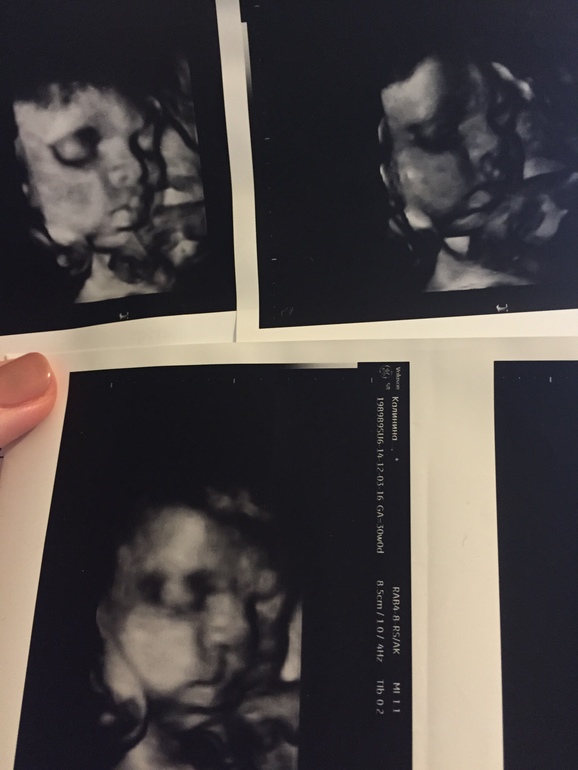

Ну да ладно, пишу по факту: мальчуган наш хорошенько вырос - в 30 неделек 1608 гр весил, по всем параметрам идем срок в срок, только ноги у нас длинные))) опережают почти на 2 недели. Уже оброс жирком, такой милый щеканчик), лежит головой вниз, обвитий пока тоже не замечено, тьфу-тьфу.. Тонуса нет, изжога помучила где-то на 28-й неделе пару дней и отпустила, пока не вернулась, и слава Богу))

Ну, и фото напоследочек): 1.УЗИ в 30 недель и наш пупс)